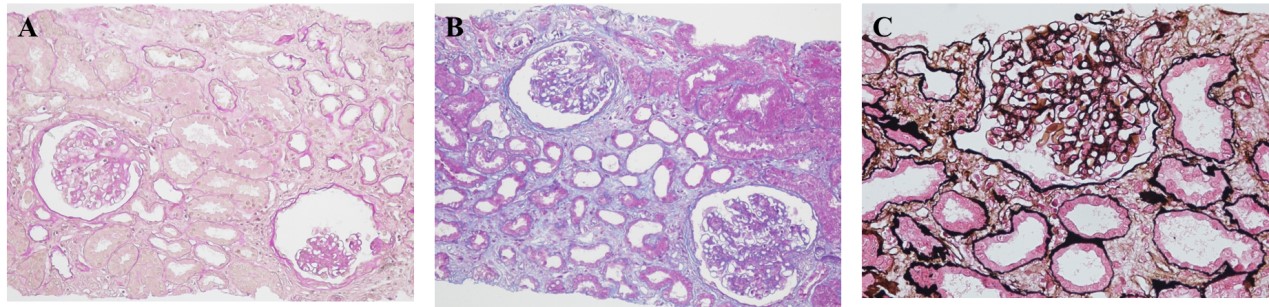

肾组织活检:(1)光镜检查(图1)镜下见2条皮髓肾穿组织常规染色切片可见6个肾小球,正切大小基本正常,部分小球球内细胞数增多,小球系膜细胞和基质轻度增生伴局灶节段性中一重度增生多数系膜区可见2~4个系膜细胞,节段系膜区增宽,基底膜未见明显病变,部分手细血管腔狭窄,节段毛细血管内细胞增多,节段系膜区可见嗜复红蛋白沉积可见1个小球伴球囊粘连。肾小管上皮细胞空泡及颗粒变性,灶状肾小管上皮细胞扁平、刷毛缘脱落伴管腔扩张,局灶性肾小管萎缩及间质纤维化(约10%),可见红细胞管型形成,肾间质局灶性水肿,局灶性淋巴、单核细胞及少量浆细胞浸润(约5~10%),部分小动脉管壁增厚,少数可见玻璃样变性。(2)免疫荧光检查(图2)镜下见1个肾小球,IgG-、IgM+、IgA+~++、C3++、C1q-、FRA-、A1b-、κ±、λ+、PLA2R-,系膜区块状沉积。(3)电镜检查(图3)镜下见1个肾小球。系膜区:节段性轻~中度增宽,系膜基质增多,系膜区、系膜旁区可见少量块状电子致密物沉积;毛细血管腔:节段性狭窄,少量内皮细胞空泡变性;基底膜:部分增厚,节段内皮下可见少量电子致密物沉积。足细胞:足突大部分融合,肾小管及间质:部分肾小管上皮细胞微绒毛脱落,肾间质少量胶原纤维增生,少量淋巴细胞、单核细胞浸润。

图 1 肾活检光镜检查。A HEx200;B PASx200;C PASMx200